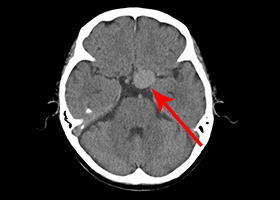

①くも膜下出血の原因となる脳動脈瘤(のうどうみゃくりゅう)の外科治療

63歳女性、左眼視力低下で発症

[画像所見]

左眼の奥に大きな動脈瘤認めます。 -